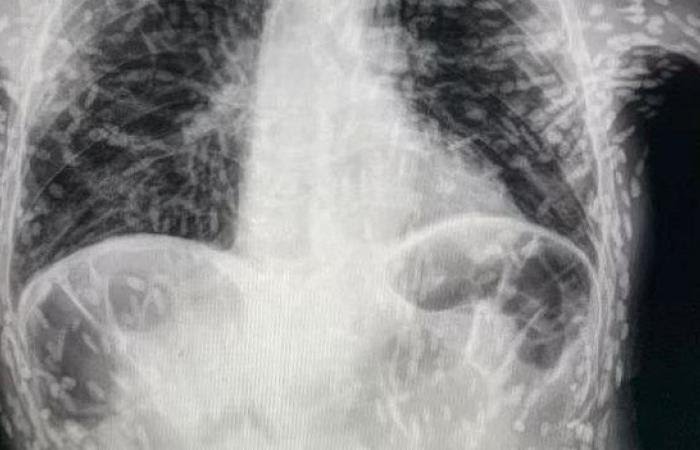

Bir doktorun Twitter’da paylaştığı röntgen, her biri bir parazitin yerleşmiş kalıntılarını temsil eden yüzlerce parlak lekeyi gösterdi.

Sistiserkoz olarak adlandırılan durum, normalde bağırsaklarda yaşayan bir tenya türünün larvalarının kas veya beyin gibi dokulara girmesiyle ortaya çıkıyor. İnsanlar, başta et ve yıkanmamış meyve ve sevze olmak üzere kontamine yiyecekleri kazara yutarak bu tenyalar ile enfekte oluyor. Larvalar, deriden hissedilebilen kistler şeklinde sert yumrular oluşturuyor.

Bununla birlikte, tenyalar hızla öldüğü için durum genellikle zararsız olarak kabul ediliyor. Ancak ölü tenyalar geride bıraktığı kistler ölüme varabilen sağlık sorunlarına neden olabiliyor. Kistler akciğerlerinize yapıştığında ise öksürük ve göğüs ağrısı oluşuyor.

Görüntüyü paylaşan Brezilya’daki Botucatu’daki Hospital das Clínicas’tan Dr. Vitor Borin de Souza, hastanın öksürük şikayetiyle geldiğini ve durumun MRI ile rontgen taramalarında anlaşıldığını söyledi.